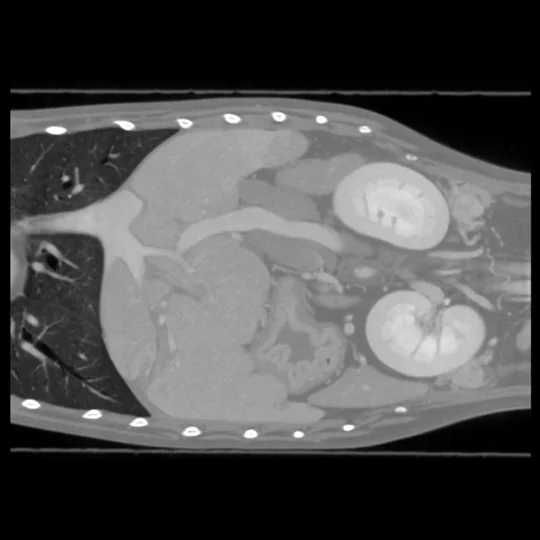

Tomografia komputerowa umożliwia kompleksową ocenę narządów klatki piersiowej, jamy brzusznej oraz miednicy, co jest szczególnie istotne w przypadkach przewlekłych, niejednoznacznych objawów klinicznych, podejrzenia nowotworów, urazów wewnętrznych lub zmian w obrębie układów: oddechowego, pokarmowego, moczowo-płciowego i limfatycznego.

W obrębie klatki piersiowej, CT pozwala na dokładne zobrazowanie miąższu płuc, opłucnej, śródpiersia, przepony oraz serca. Jest niezastąpiona w wykrywaniu guzów płuc, rozedmy, krwiaków, ciał obcych oraz przerzutów nowotworowych. Zastosowanie kontrastu umożliwia dodatkowo ocenę naczyń klatki piersiowej.

W diagnostyce jamy brzusznej, tomografia pozwala na ocenę narządów takich jak wątroba, śledziona, trzustka, nerki, nadnercza, przewód pokarmowy oraz pęcherz moczowy. Umożliwia wykrycie guzów, torbieli, kamieni, zmian zapalnych, perforacji oraz niedrożności jelit. TK umożliwia po podaniu kontrastu zobrazować położenie przecieku wrotno-wątrobowego (ZWO).

W obrębie miednicy, CT służy do diagnozowania złamań, uszkodzeń stawów biodrowych, guzów prostaty, zmian w pęcherzu moczowym, pochwie, macicy oraz okolicznych węzłach chłonnych. Szczególnie cenne jest trójwymiarowe obrazowanie struktur kostnych w przypadkach urazów lub wrodzonych deformacji.